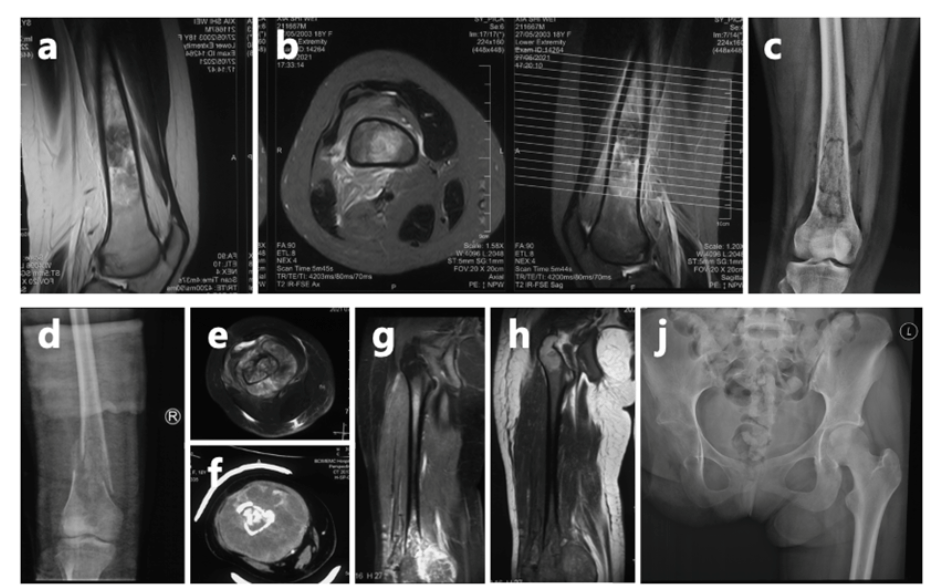

上海市第一人民医院骨肿瘤科讲述了夏夏的最新情况:她经历了6次手术和无数次挑战,自2023年8月接诊以来,又完成了10次化疗和2次手术皇冠信用盘代理 。尽管困难重重,她始终以微笑和坚韧面对一切。

夏夏前期接受了术前化疗、截肢手术及术后化疗,使用的是一线化疗方案皇冠信用盘代理 。然而,结疗不到一年,肺部出现转移病灶,经过手术切除后未再进行化疗。术后5个月,左肺再次发现新发转移病灶。

2024年11月,夏夏接受胸腔镜下右肺下叶切除术皇冠信用盘代理 。2025年1月复查:右肺术后改变。